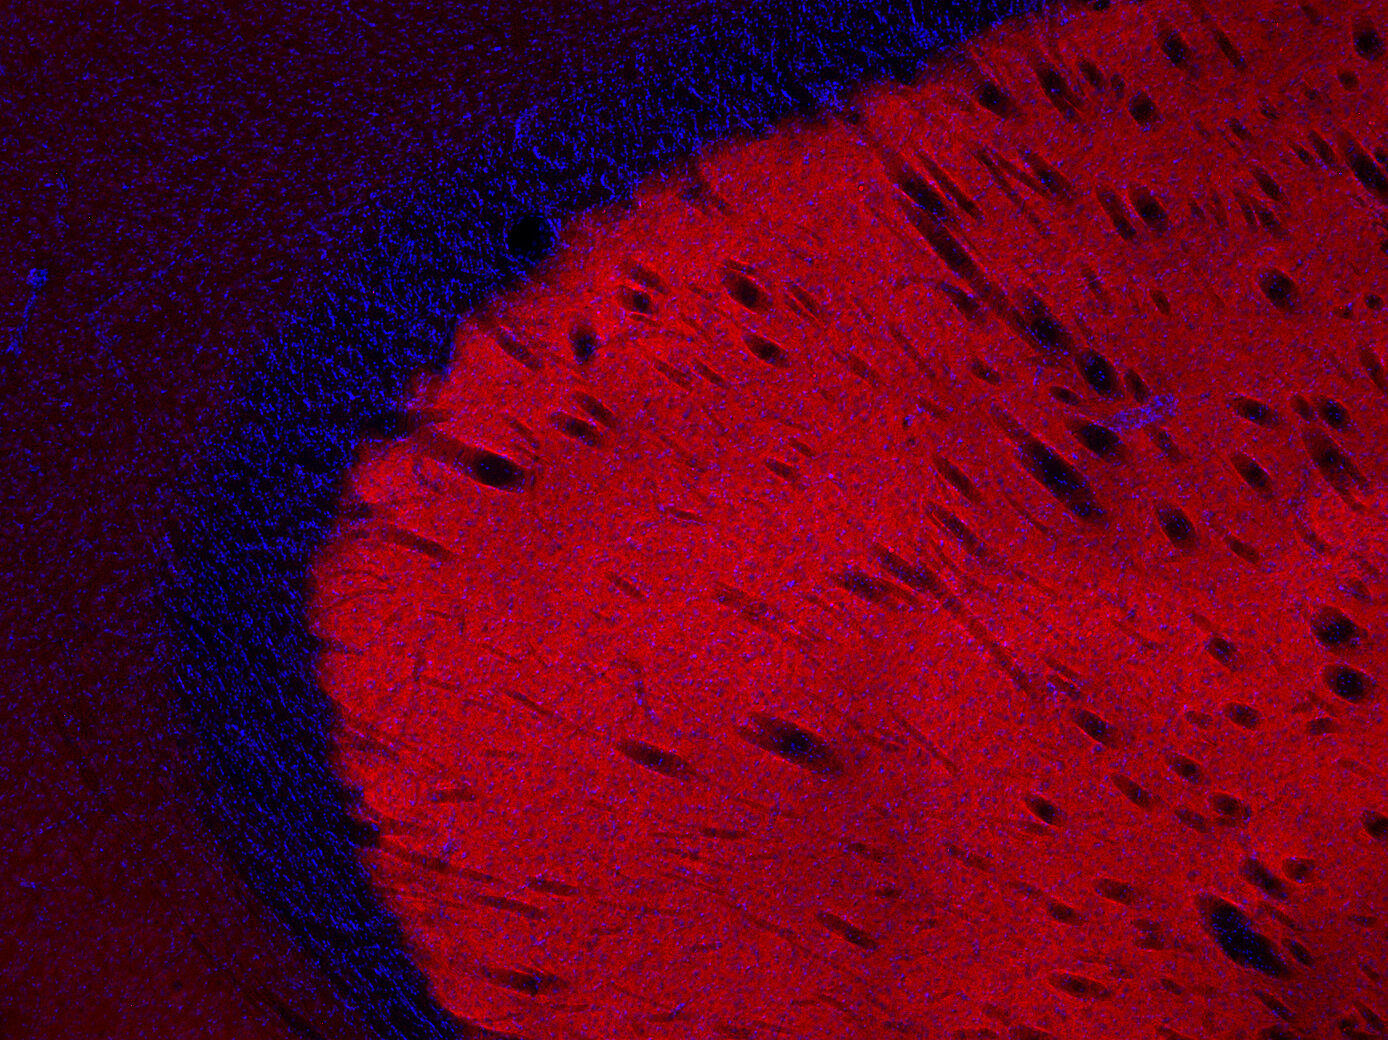

Dopamine receptor D1 antibody - 376 002

IHC: 1 : 500 gallery

IHC-P: 1 : 500 gallery

Specificity Specific for dopamine receptor D1. The antibody may have a weak crossreactivity to dopamine receptor D5.

Dopamine receptor D1 is widely distributed throughout the brain with the highest expression in the striatum. In the periphery, the D1 receptor has been detected in the adrenal cortex, kidney and heart. Recently, it was shown that dopamine receptor D1 is expressed in breast cancer, thereby identifying this receptor as a novel therapeutic target in this disease. D1 receptor overexpression is associated with advanced breast cancer and poor prognosis.